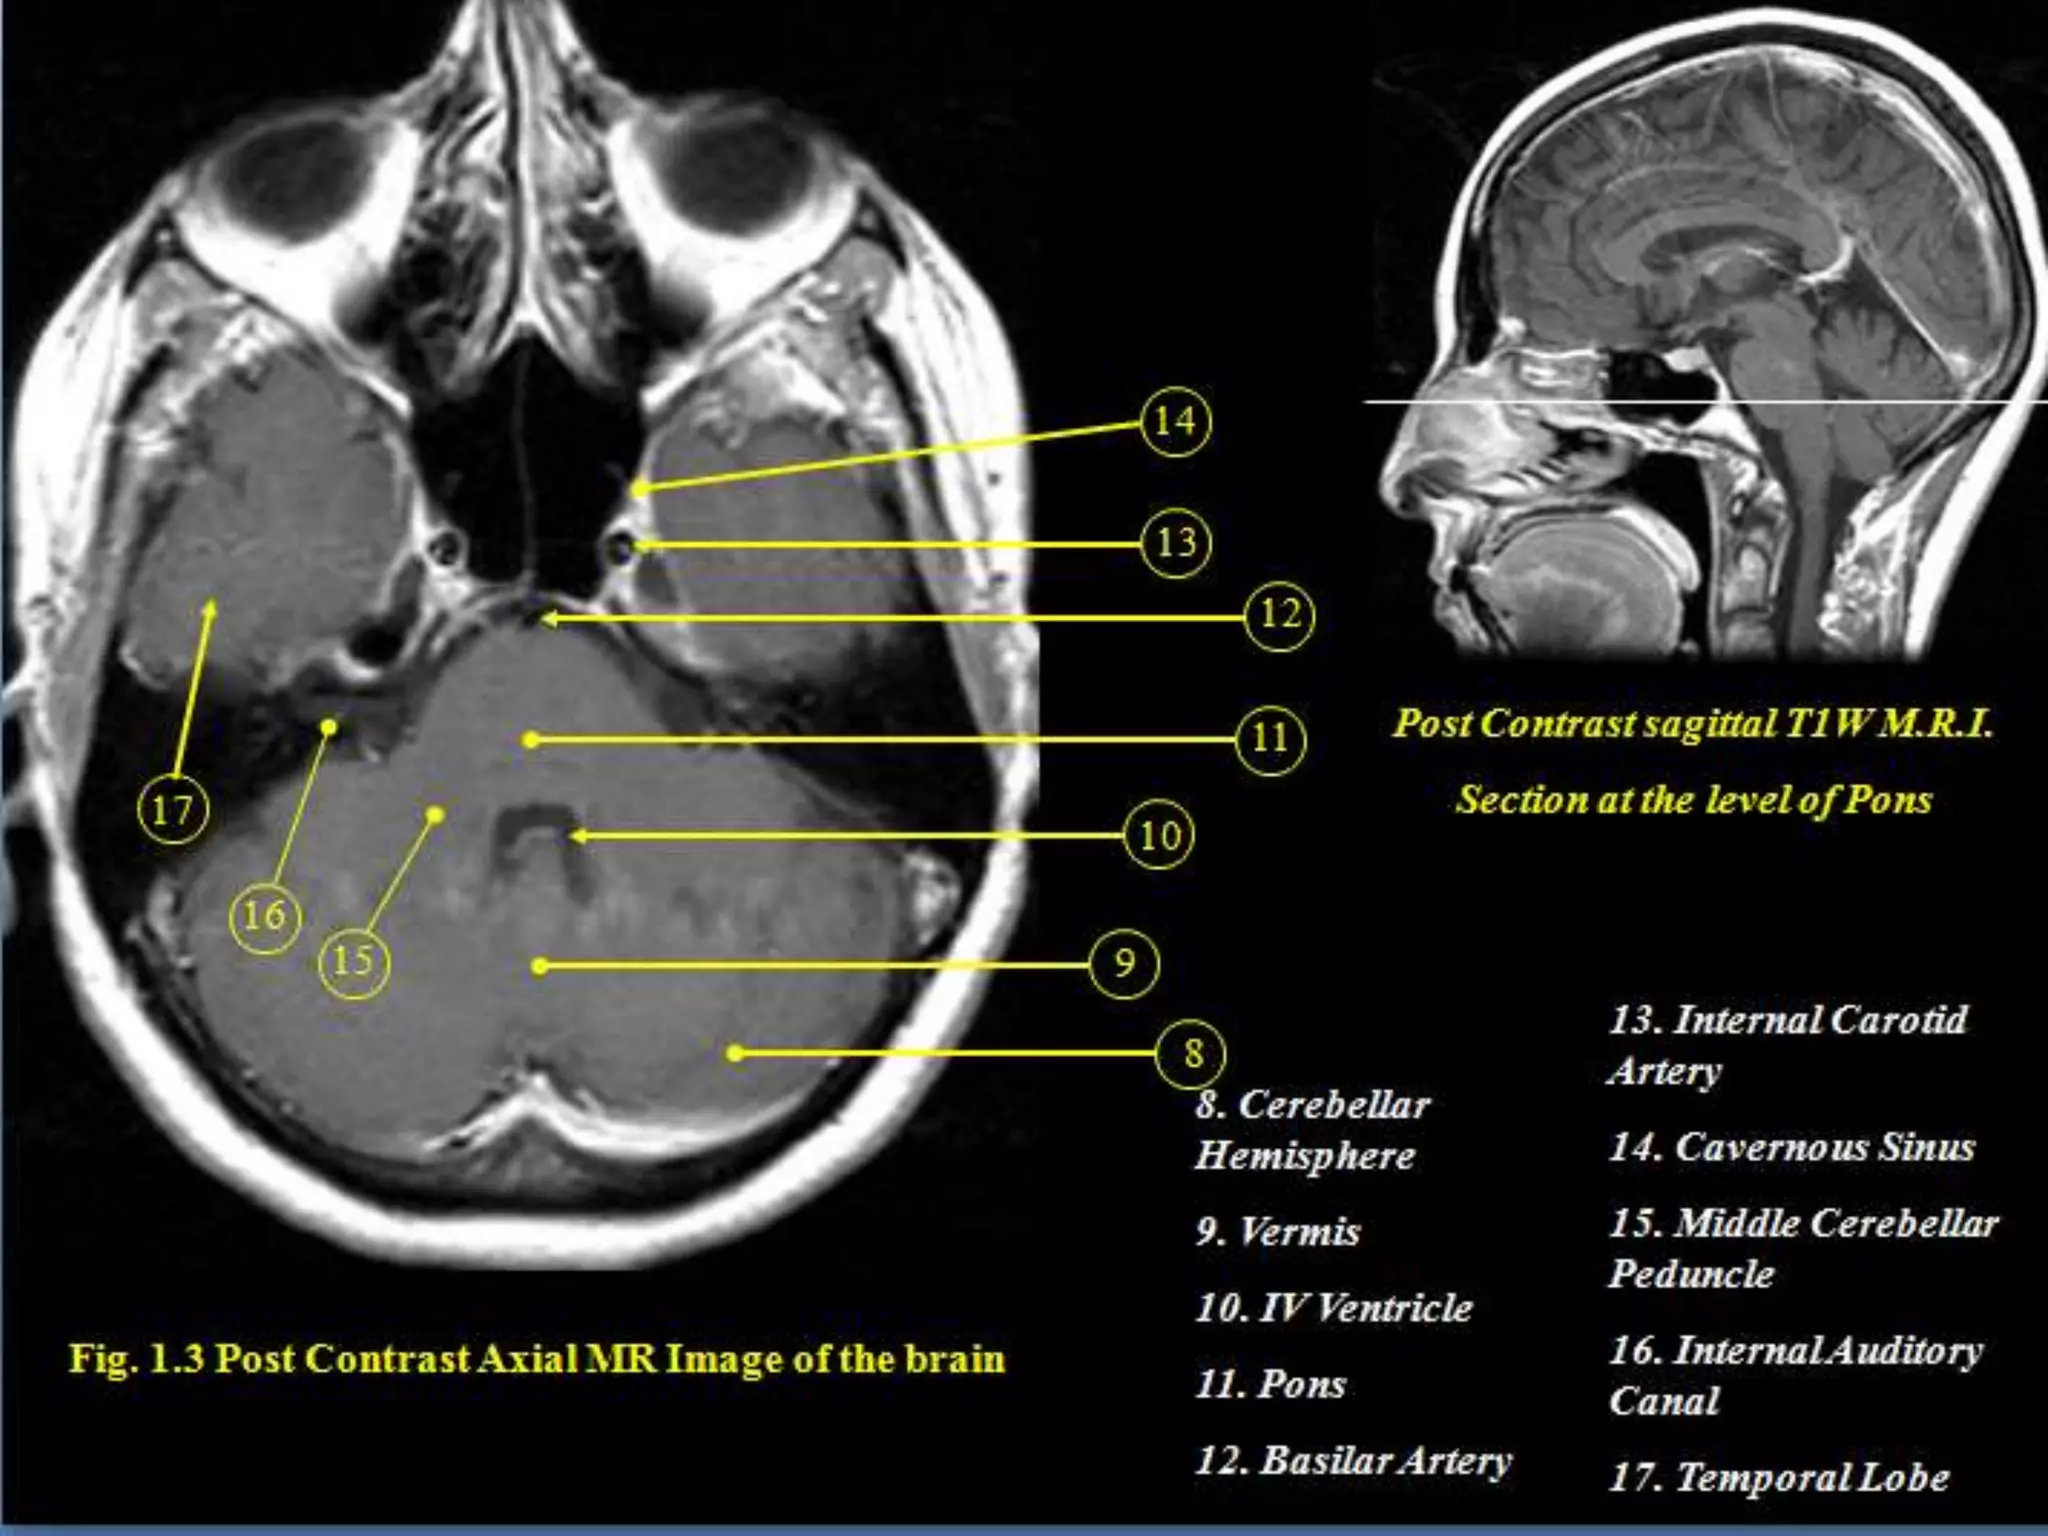

Sectional Anatomy: NormalAxial CT and MRI Anatomy. On CT and MR scans, the brain has been briefly viewed in infratentorial and supratentorial sections, as described below. CT scans are performed with a 15- to 20-degree angulation to the canthomeatal line at 8-mm increments. MRI scans are generally obtained parallel to the AC-PC line in the axial plane with 6-mm slice thickness. Using the sagittal view, the coronal sections are acquired parallel to the brain stem, and the sagittal sections are obtained perpendicular to the axial section. On MRI studies, cranial nerves IX and X can be demonstrated at this level because they emerge from the postolivary sulcus. The posterior aspect of the cerebellar hemispheres is outlined by the inferior portion of the cisterna magna.